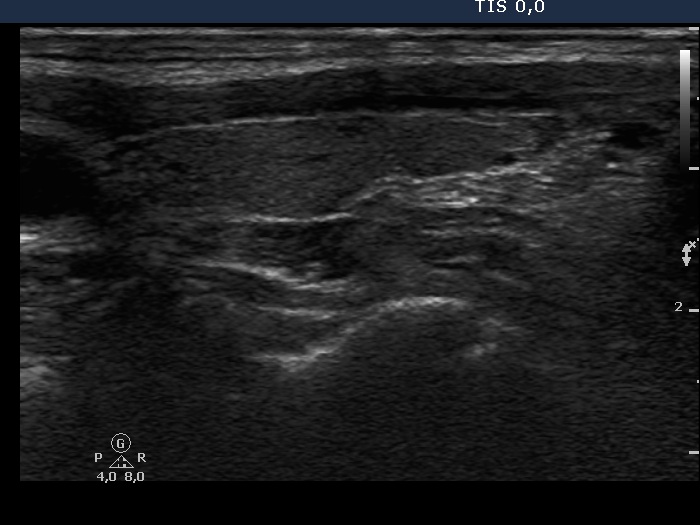

Oxyphilic adenoma - Case 5. (ultrasonographic picture 6)

Left lobe, longitudinal scan. There are several small hypoechogenic lesions within an echonormal background.